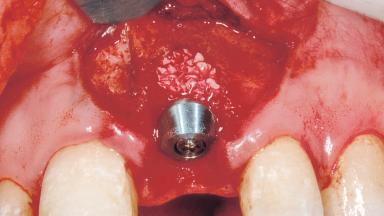

Immediate Placement of an Implant in a Maxillary Left Central Incisor Site

A 33-year-old female patient presented with an upper left central incisor that required extraction after a failed endodontic therapy. The tooth had been traumatized when the patient was a teenager and had undergone several endodontic treatments, including two apicectomy procedures. The patient was in good health and did not smoke. Clinical examination showed that the patient had a high lip line. In full smile, the gingival margins of the upper teeth were visible to the first molars. The gingival margins of central incisors 11 and 21 were only just showing. Examination of tooth 21 confirmed that the tooth was mobile and had hypererupted by 1 mm.

Placement Protocol | Immediate implant placement |

Tooth Site | Maxillary incisor or canine |

Socket Morphology | Single-root socket |

Socket Integrity | Damage to one or more bone walls |